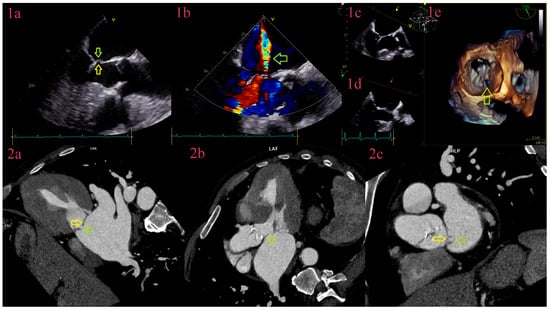

3.3. Vegetations

3.4. Aneurysms

3.5. Perforations

3.6. Abscesses

3.7. Pseudoaneurysms

3.8. Fistulas

3.9. Leaks